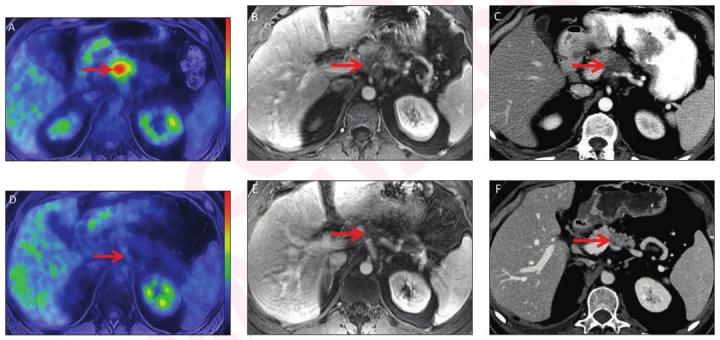

image: Pre-treatment (A-C) and post-treatment (D-F) images after eight cycles of systemic FOLFIRINOX and consolidative chemoradiation. Baseline CA 19-9 was 145 U/ml. Pre-treatment whole body axial fused PET/MRI showed FDG avid lesion in body of pancreas (arrow, A) with SUVmax 7.1 and SUVgluc 8.0. Lesion was hypo-enhancing on axial contrast-enhanced T1-weighted (T1W) MR image (arrow, B) from focused abdominal PET/MRI and on CT (arrow, C). Pre-treatment CT tumor volume was 10.3 cm3. Post-treatment whole body axial fused PET/MRI showed complete metabolic response (arrow D) with SUVmax 1.9 and SUVgluc 1.9. Lesion was indistinct on axial contrast-enhanced T1W MRI (arrow, E) and CT (arrow, F), and there was upstream pancreatic parenchymal atrophy. Post-treatment CT tumor volume was 0.46 cm3. There was normalization of CA 19-9. Relative change in SUVmax (ΔSUVgluc) was -73%, and relative change in SUVgluc (ΔSUVgluc) was -76%. Based on change in tumor size, response was categorized as partial response per RECIST. Relative change in tumor volume (ΔTvol) was -96%. Pathology showed major pathologic response (College of American Pathologists score 1.)